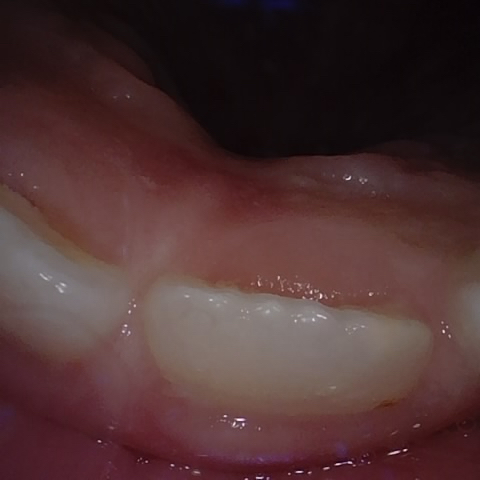

Annotated as "Good"